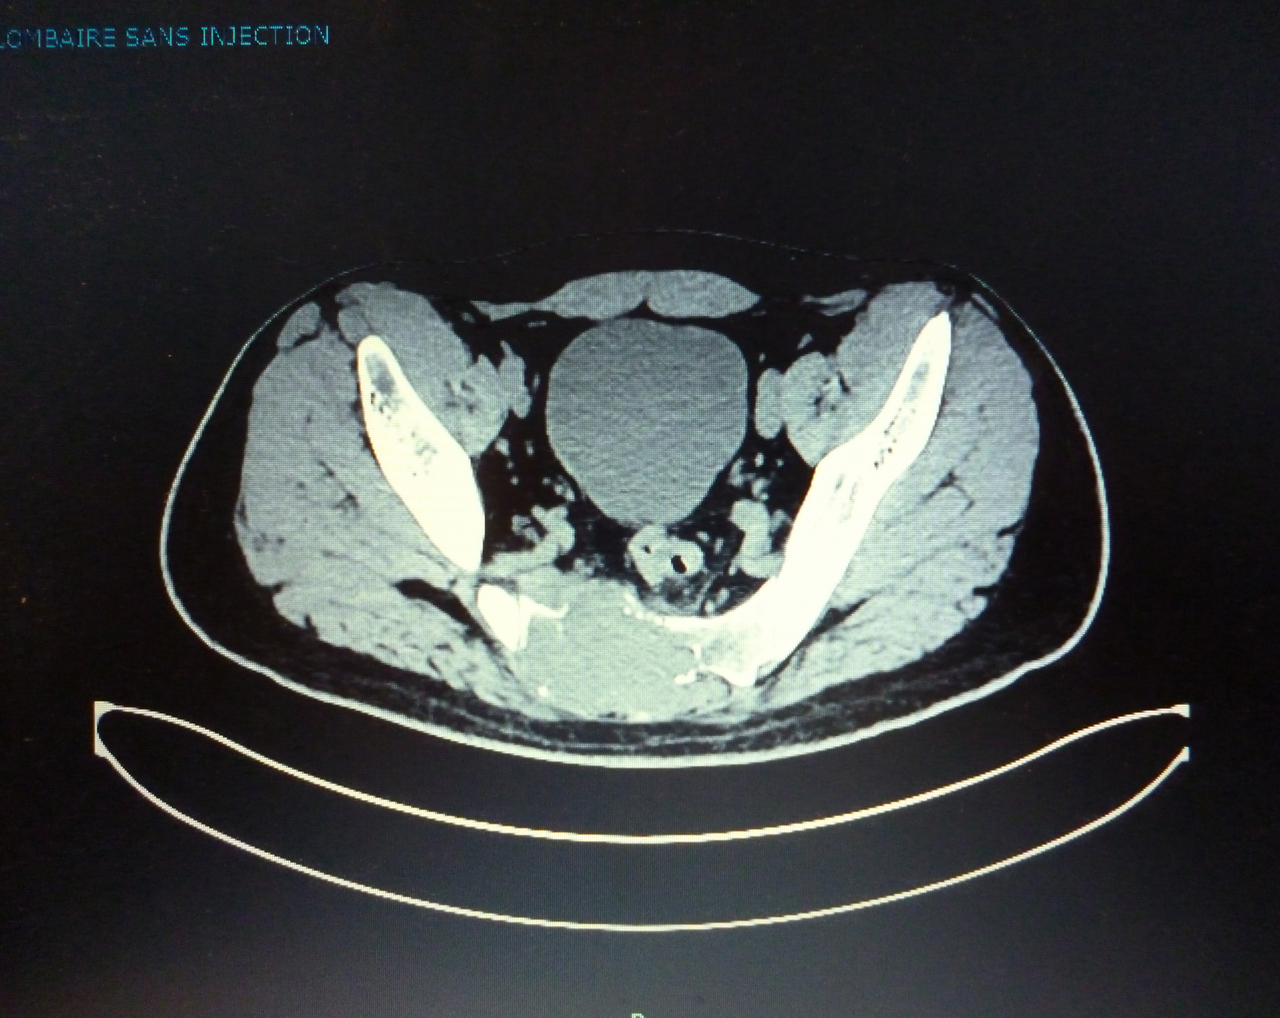

Quel est votre diagnostic ?

Il s'agit d'un chondrosarcome.